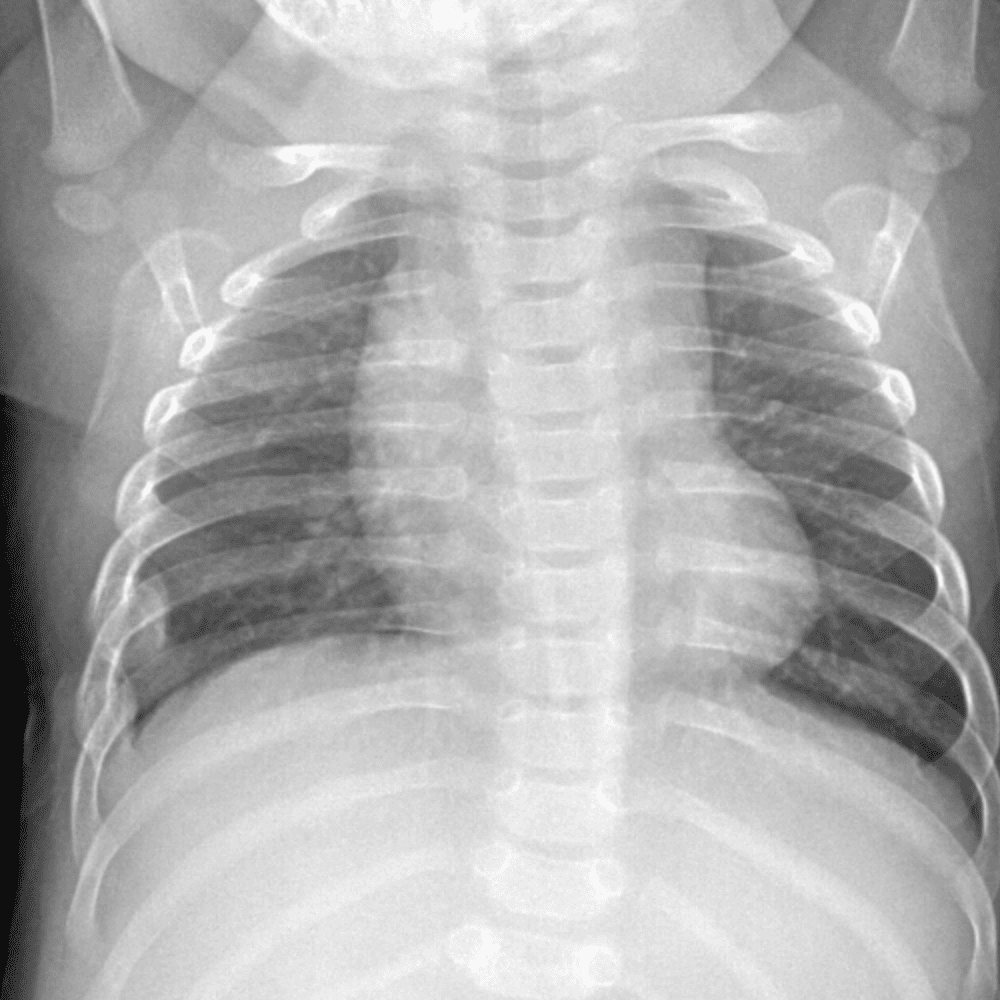

Peds Chest

Practice

Simulates call by including subtle or difficult cases and some normals.

50 cases